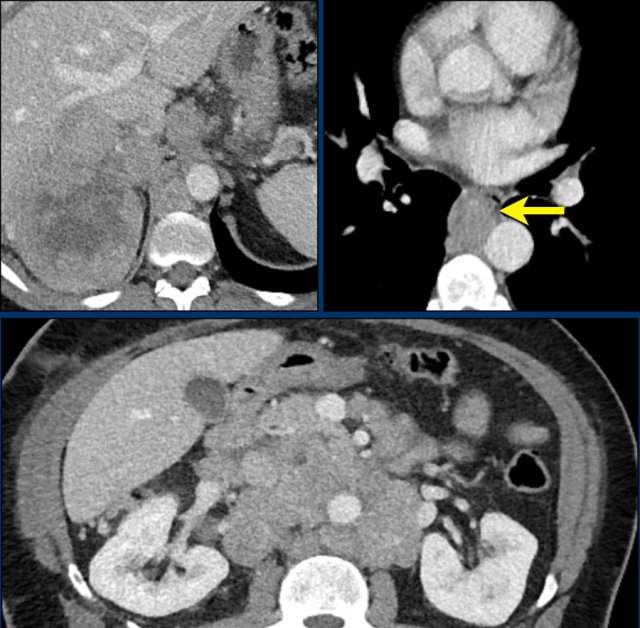

Axial and coronal CT images in a patients with a right adrenal carcinoma and extensive IVC invasion.

The coronal image also shows tumor extension into the right renal vein.

Axial and coronal CT images of another patient with an adrenal carcinoma with extensive IVC invasion (yellow arrow).

IVC and renal vein tumor invasion are seen in up to 20% of patients.